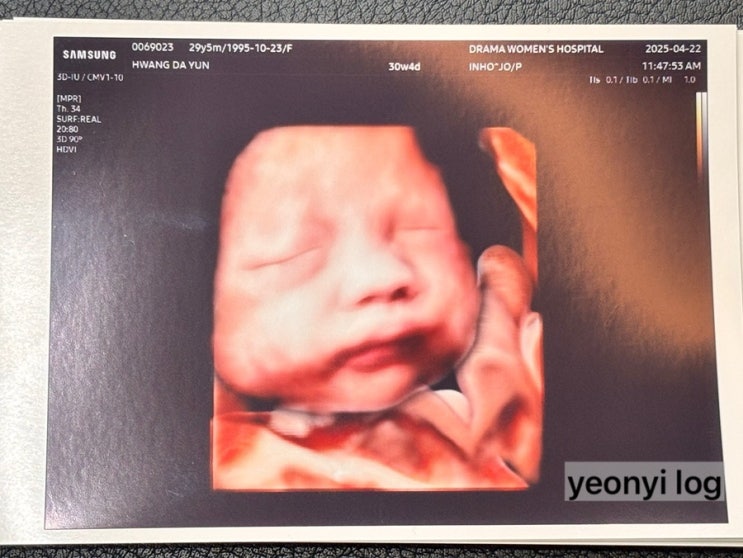

임신 29주 ~ 30주 기록 및 일상

임신 29주차 ~ 30주 기록 및 일상 [ 29주차 ] 4. 11. 딱 29주차 진입한 날, 엄마 생신이라 가족들 다같이 ...